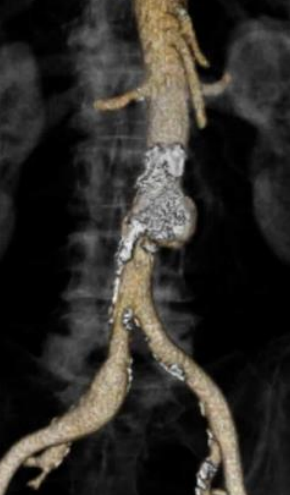

Nello specifico, “presso il nostro ambulatorio, da circa 4 anni era in follow up un paziente di 80 anni, portatore di una PAU (Ulcera Aterosclerotica Penetrante) dell’aorta addominale. In anamnesi riferiva ipertensione, dislipidemia, pregresso intervento alla prostata, cardioversione per fibrillazione alcuni anni prima e, attualmente, terapia con anticoagulante sempre, per la fibrillazione. Il paziente era asintomatico, anche all’ultimo controllo, ma abbiamo assistito a un repentino incremento della profondità della lesione che è passato in poco più di 6 mesi da 0,8 mm a 20 mm”, prosegue la dottoressa Socrate.

L’ulcera penetrante aterosclerotica (PAU) dell’aorta è una patologia che si riscontra, prevalentemente, in aorta toracica, eccezionalmente in aorta addominale (circa 1% dei casi): caratteristicamente, questa lesione si sviluppa nei pazienti anziani, con un’aterosclerosi sistemica.

In anestesia locale e sedazione, mediante un accesso mini-invasivo - percutaneo, è stata impiantata la protesi con un particolare accorgimento tecnico (invertendo la protesi su banco) che ha consentito di riparare la lesione, senza aprire l’addome.